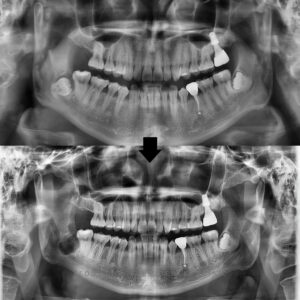

환자분께서는 오래전 치료했었던

앞니 브릿지가 심미적으로 안좋고

충치도 생긴 것 같다며 상담을 위해

본원에 내원해 주셨습니다.

확인해 보니,

보철이 오래되면서 잇몸 퇴축이 진행되어

브릿지 경계 부위가 노출되어 있었고,

그로 인해 심미적인 불만뿐 아니라

보철 하방으로 충치가 의심되는

상태였습니다.

특히 앞니 롱 브릿지 특성상

위생 관리가 쉽지 않아,

장기간 사용하면서 치아와 잇몸에

부담이 누적된 것으로 판단되었습니다.